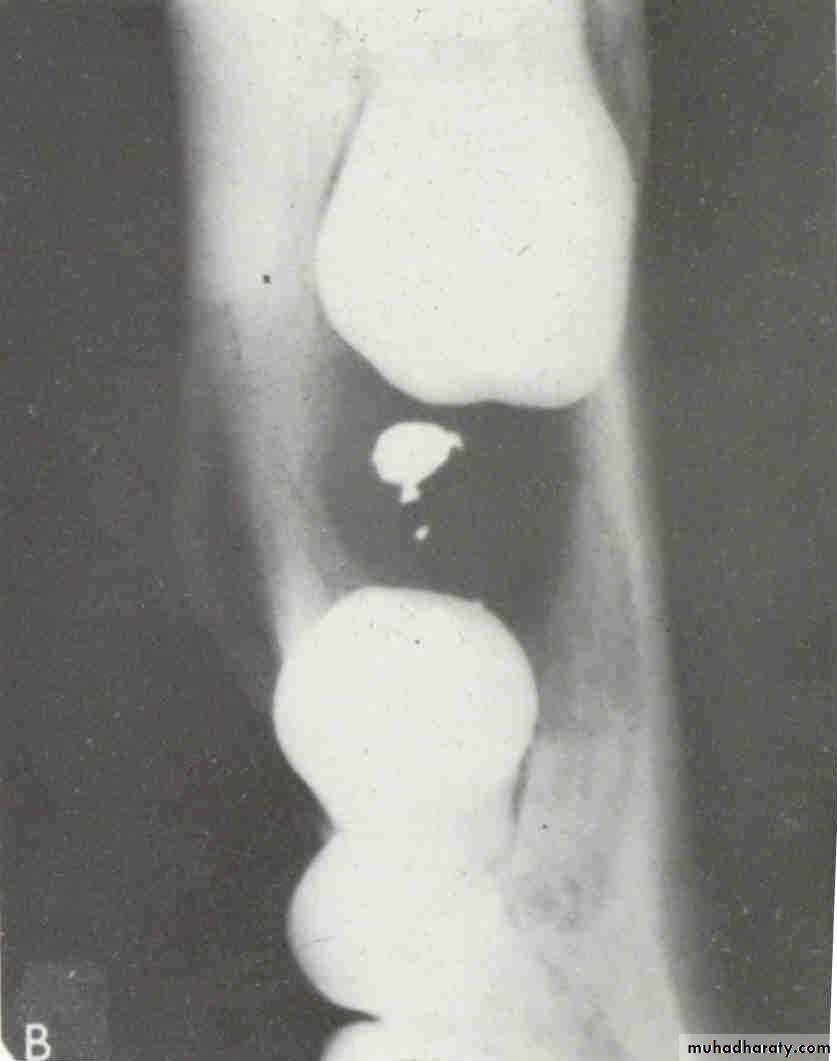

FOREIGN BODYWATERS VIEW(Occipitomental )

LATERAL VIEWLateral oblique